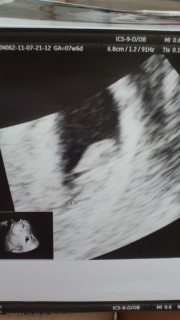

1週間で倍以上おっきくなってた!! 8.2ミリで相応の大きさだそうです。 次から出産予定の病院へ☆ 大きくなれよー

前回は胎嚢のみでしたが胎芽と元気な心拍を確認できました(^^)胎芽11.0mmのちっちゃい体で一生懸命心臓チカチカさせてました~次の二週間後が楽しみです!

前回の検診から2週間、7w4dで、10,9㎜の赤ちゃんの心拍を確認しました(^.^)次はまた、2週間後の診察。予定日が決まるみたいで、楽しみです☆

5日前の診察から4ミリ大きくなって赤ちゃん11ミリでした。出血あって心配だったけど育ってくれてて良かった♪今回は卵黄嚢も見れて、心臓がピコピコ動いてるのも分かりました。母子手帳もget☆